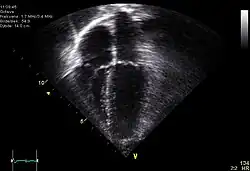

| Diagnostic method | ECG, chest x-ray, bedside echocardiogram |

Diagnosis of traumatic cardiac arrest is initially made with electrocardiogram with EMS or in the emergency department. Clinicians will also order diagnostic testing that may include chest x-ray, bedside ultrasound and echocardiogram, and blood gas levels. A type and cross will be ordered to match the patient to receive blood transfusion if necessary.